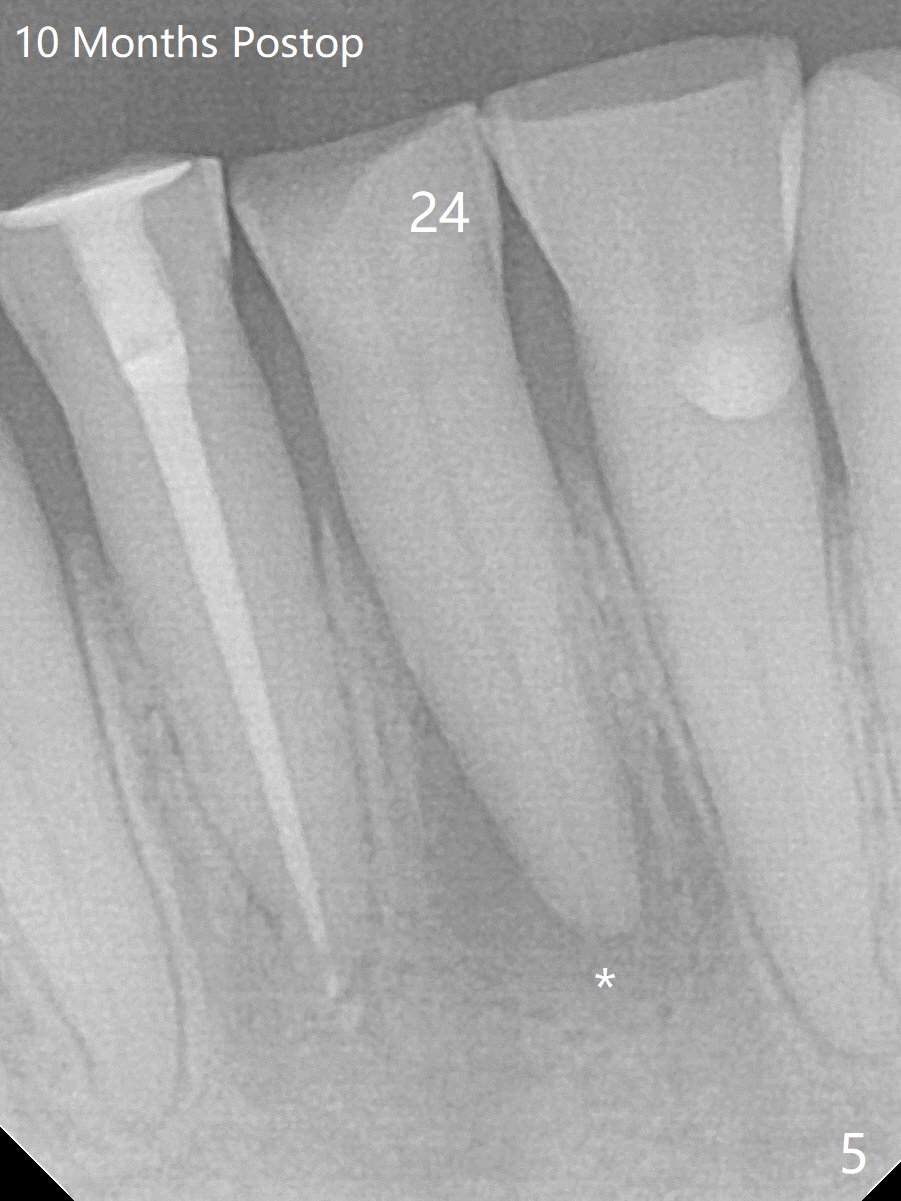

A 64-year-old man has multiple restoration and loves to eat crab. The lower incisors have severe wear. The tooth #25 is discolored with pulpal exposure and periapical radiolucency (Fig.1, 2 *). After insertion of 30/.04 master cone (Fig.3 (1 year 3 months post diagnosis)), RCT is finished with BioRoot RCS (bioceramic) and single GP (Fig.4). Nearly 10 months later, the patient returns with sinus track associated with the tooth #24 with PARL (Fig.5 *).